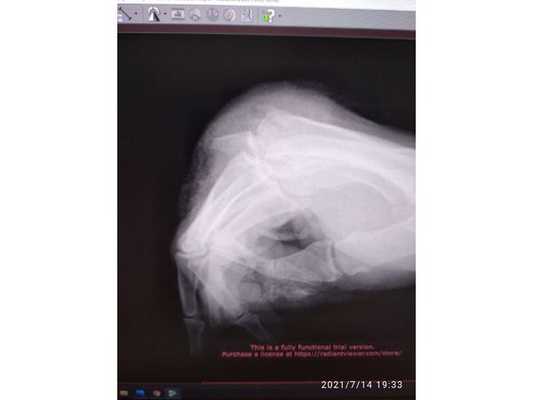

Кожа на правой руке тёплая. Верхняя и средняя фаланги большого пальца соединены со следующей (проксимальной) фалангой лоскутом кожи. Также у основания проксимальных фаланг оставшихся пальцев находились рваные раны. В них были видны части сломанных костей и повреждённые концы сухожилий-разгибателей.

- ампутацию на уровне головки нижней фаланги большого пальца;

- оскольчатый отрывной перелом основания нижней фаланги указательного пальца;

- вынужденное сгибание средних фаланг кисти.